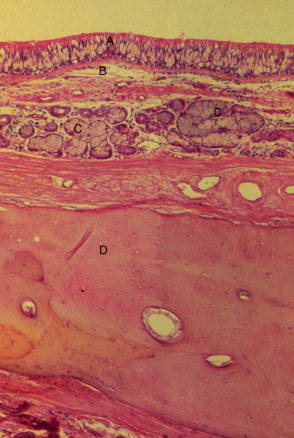

K-slide 34: Still higher magnification of slide 32

A. Respiratory epithelium of nasal cavity

B. Lamina propria

C. Seromucous glands within submucosa of nasal cavity

D. Bone